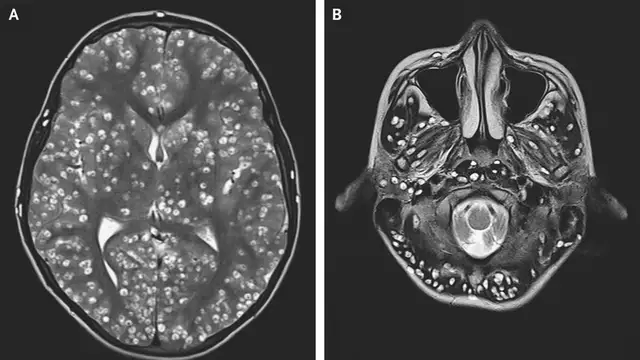

Según informa New England Journal of Medicine, un joven de 18 años ha fallecido en la India por una plaga de tenias parasitarias de cerdo en el cerebro, conocidas como Taenia solium.

El chico ingresó en el hospital con dolor de cabeza, convulsiones, sensivilidad en el testículo derecho y el ojo derecho hinchado. Las pruebas médicas revelaron que tenía varias lesiones en el cerebro y cerebelo causadas por los gusanos que tenía en el interior.

La plaga le provocó una infección, la cisticercosis, que le atacó el tejido muscular.